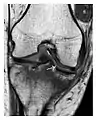

- a

- b

Figure 9: Proximal metaphyseal fatigue fracture of the tibia in a 27-year-old recent male military recruit. (a) Anteroposterior radiograph is within normal limits. (b) Coronal T1-weighted MR image shows a marked linear hypoattenuation along the medial tibial metaphysis (arrow) surrounded by diffuse hypointensity in keeping with posttraumatic edema.[1]